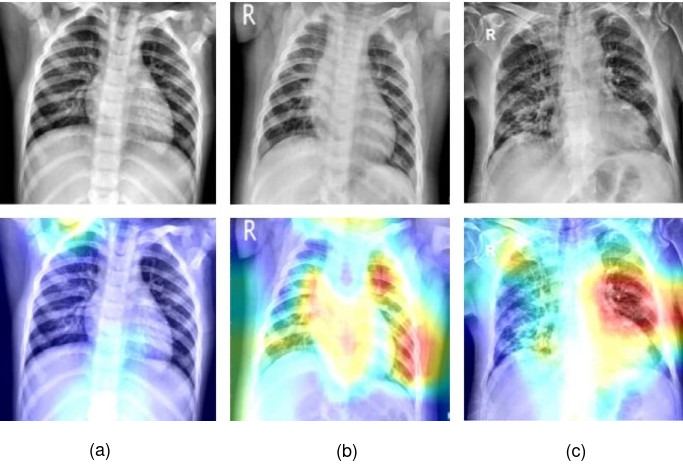

The performance of the proposed model is measured through a receiver operating characteristic (ROC) curve, as shown in Fig. 5. It demonstrates the comparison of True Positive Rate (TPR) vs False Positive Rate (FPR) between the proposed model and the baseline and sub-models. Generally, the larger area covered by the curve represents the highest accuracy model. It is visible that the proposed multilayer multimodal fusion model has the highest area compared to other comparable models. Moreover, to enhance the interpretability our proposed model, we utilized Gradient-weighted Class Activation Mapping (Grad-CAM), which effectively elucidates the model’s decision-making process. This class activation map is generated by channeling gradient information from CXR images back into the final convolutional layer, allowing us to discern the significance of each neuron in classifying images into different disease classes. Fig. 6 showcases the class activation maps for CXR images of COVID-19, Pneumonia, and Normal cases. In these maps, light colors (such as blue) represent clear lungs, while hot colors (like red and yellow) indicate areas of infection in the lungs. Therefore, it is evident from the class activation maps of COVID-19 and Pneumonia that infected lungs display a hot color, while normal lungs appear in a lighter color (blue). These activation maps serve as a valuable tool for healthcare professionals to visualize the lungs and highlighting the infected areas. These results indicate that the proposed model is a better classifier for COVID-19 and Pneumonia diseases.